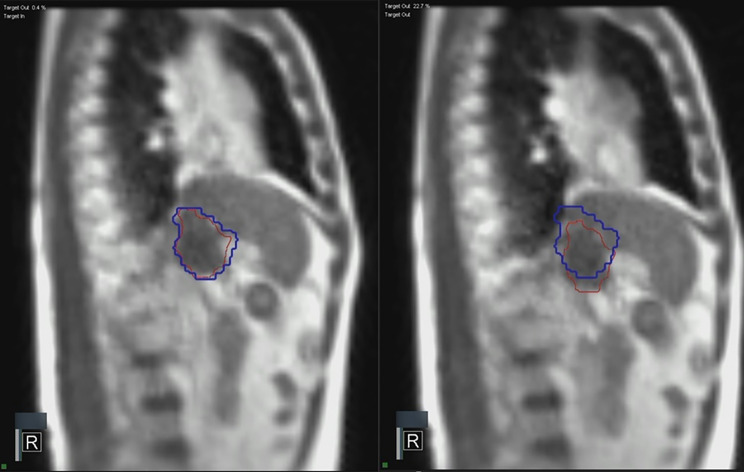

Background: High-dose prescribed radiotherapy has been attempted to improve local control and restore portal vein in patients with hepatocellular carcinoma (HCC) complicated with portal vein tumor thrombus (PVTT). The aim of this study was to evaluate feasibility of real-time tumor-tracking magnetic resonance imaging-guided radiotherapy (rtMRgRT) for PVTT in HCC. In addition, prognostic factors for overall survival (OS) and progression pattern after radiotherapy (RT) were analyzed.

Methods: We retrospectively reviewed the data of 34 patients who had unresectable HCC complicated with PVTT and who were treated with rtMRgRT using hypofractionated radiotherapy (HFRT) and stereotactic body radiation therapy (SBRT) between June 2019 and October 2023. HFRT was performed with a total of 50-60 Gy in 10 fractions, and SBRT was performed in a range of 36-50 Gy in 4-5 fractions. The median biologic effective dose with an a/b ratio of 10 was 100 Gy10 (range: 68.4-100 Gy10).